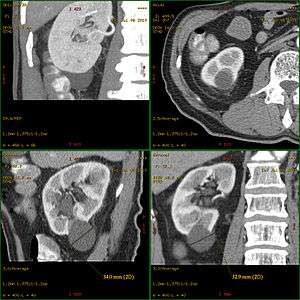

A renal cyst or kidney cyst, is a fluid collection in or on the kidney. There are several types based on the Bosniak classification. The majority are benign, simple cysts that can be monitored and not intervened upon. However, some are cancerous or are suspicious for cancer and are commonly removed in a surgical procedure called nephrectomy.

Bosniak classification

Renal cysts are classified as either malignant or benign using the Bosniak Classification System. The system was created by Dr. Morton Bosniak, a faculty member at the New York University Langone Medical Center in New York City.[2]

The Bosniak classification categorizes renal cysts into five groups.[3]